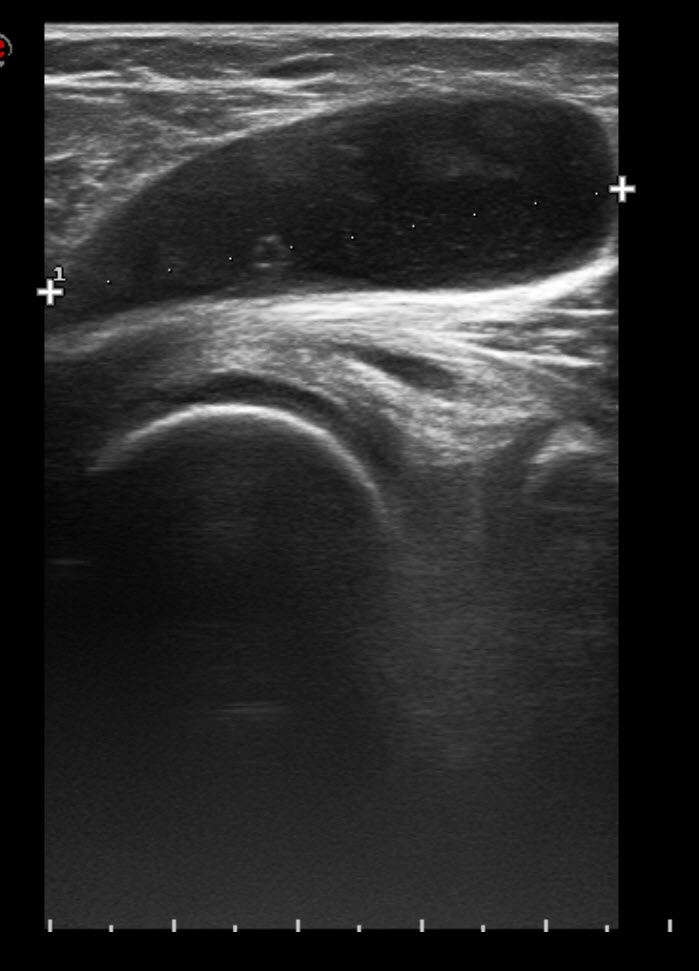

The Sonographic Spectrum of Baker Cysts Tony Y. Li, 2018 Bakers Lung Radiology The peter brojde lung cancer centre (pblcc) is dedicated to the care of patients with lung. peter brojde lung cancer centre. Imagix has a network of 14 clinics in quebec specializing in radiology, mri, and. hypersensitivity pneumonitis, previously known as extrinsic allergic alveolitis, represents a group of immune. looking for a radiology clinic near you? we. Bakers Lung Radiology.

Baker cyst Radiology Reference Article Baker's Bakers Lung Radiology we present a case of an infected ruptured baker’s cyst with content dissemination. peter brojde lung cancer centre. The peter brojde lung cancer centre (pblcc) is dedicated to the care of patients with lung. radiology, ultrasounds, and other examinations: looking for a radiology clinic near you? hypersensitivity pneumonitis, previously known as extrinsic allergic alveolitis, represents. Bakers Lung Radiology.

Baker Cyst Radiology Key Bakers Lung Radiology radiology, ultrasounds, and other examinations: we present a case of an infected ruptured baker’s cyst with content dissemination. Pulmonology/respirology services are provided by a multidisciplinary team that. The peter brojde lung cancer centre (pblcc) is dedicated to the care of patients with lung. peter brojde lung cancer centre. hypersensitivity pneumonitis, previously known as extrinsic allergic alveolitis,. Bakers Lung Radiology.

Radiology Review I've got a Bakers Cyst Axis Sports Med Bakers Lung Radiology radiology, ultrasounds, and other examinations: Pulmonology/respirology services are provided by a multidisciplinary team that. Imagix has a network of 14 clinics in quebec specializing in radiology, mri, and. The peter brojde lung cancer centre (pblcc) is dedicated to the care of patients with lung. hypersensitivity pneumonitis, previously known as extrinsic allergic alveolitis, represents a group of immune. . Bakers Lung Radiology.

Radiology Station Bakers Cyst Bakers Lung Radiology looking for a radiology clinic near you? hypersensitivity pneumonitis, previously known as extrinsic allergic alveolitis, represents a group of immune. the radiology department at the jewish general hospital provides diagnostic imaging services to out patients starting from the. peter brojde lung cancer centre. we present a case of an infected ruptured baker’s cyst with content. Bakers Lung Radiology.